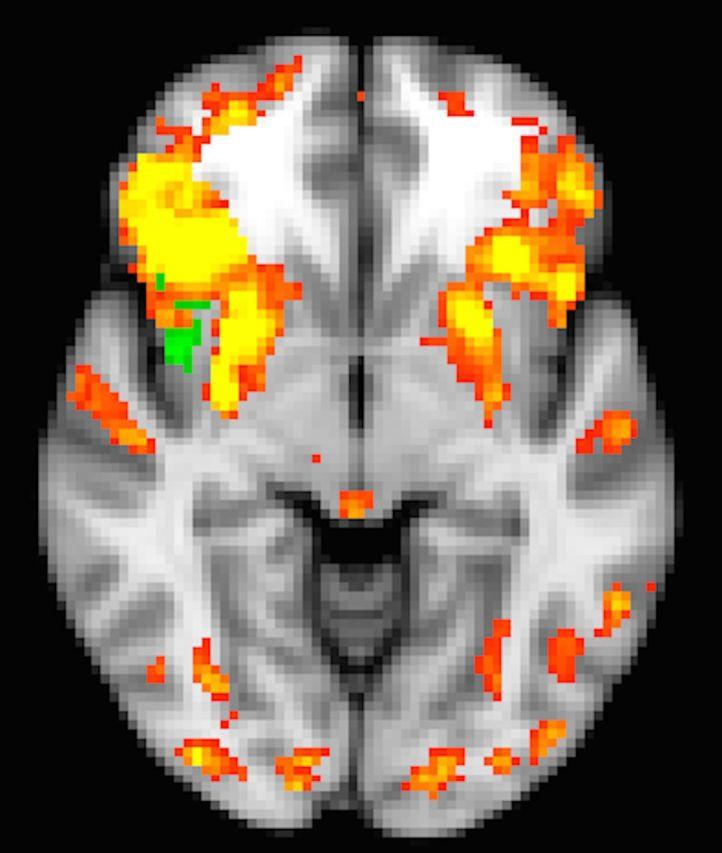

Recent advances with functional connectivity magnetic resonance imaging have demonstrated that at rest the brain exhibits coherent activity within a number of spatially independent maps, normally called 'intrinsic' or 'resting state' networks. These networks support cognition and behaviour, and are altered in neurodegenerative disease. However, there is a longstanding perspective, and ample functional magnetic resonance imaging evidence, demonstrating that intrinsic networks may be fractionated and that cortical elements may participate in multiple intrinsic networks at different times, dynamically changing alliances to adapt to cognitive demands. A method to probe the fine-grained spatiotemporal structure of networks may be more sensitive to subtle network changes that accompany heterogeneous cognitive deficits caused by a neurodegenerative disease such as Parkinson's disease. Here we tested the hypothesis that alterations to the latent (hidden) structure of intrinsic networks may reveal the impact of underlying pathophysiologic processes as assessed with cerebrospinal fluid biomarkers. Using a novel modelling approach that we call 'network kernel analysis', we compared fine-grained network ensembles (network kernels) that include overlapping cortical elements in 24 patients with Parkinson's disease (ages 45-86, 17 male) and normal cognition or mild cognitive impairment (n = 13), and 21 cognitively normal control subjects (ages 41-76, nine male). An omnibus measure of network disruption, calculated from correlations among network kernels, was correlated with cerebrospinal fluid biomarkers of pathophysiological processes in Parkinson's disease: concentrations of α-synuclein and amyloid-β42. Correlations among network kernels more accurately classified Parkinson's disease from controls than other functional neuroimaging measures. Inspection of the spatial maps related to the default mode network and a frontoparietal task control network kernel showed that the right insula, an area implicated in network shifting and associated with cognitive impairment in Parkinson's disease, was more highly correlated with both these networks in Parkinson's disease than in controls. In Parkinson's disease, increased correlation of the insula with the default mode network was related to lower attentional accuracy. We demonstrated that in an omnibus sense, correlations among network kernels describe biological impact of pathophysiological processes (through correlation with cerebrospinal fluid biomarkers) and clinical status (by classification of patient group). At a greater level of detail, we demonstrate aberrant involvement of the insula in the default mode network and the frontal frontoparietal task control network kernel. Network kernel analysis holds promise as a sensitive method for detecting biologically and clinical relevant changes to specific networks that support cognition and are impaired in Parkinson's disease.